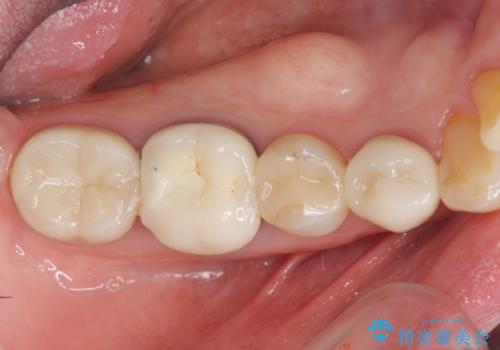

目立つゴールドをセラミックで白くしたい

- 笑った時に目立つゴールド修復を、白く自然なセラミック治療に置き換えたいとセラミック治療を希望され来院されました。

X線検査により、ゴールド修復下に虫歯の再発を多数認めました。

ゴールドの除去後に虫歯を丁寧に除去、セラミックにて自然な美しさを回復できるよう治療を計画します。

- 34.1万円(ジルコニアクラウン×2・仮歯×2・セラミックインレー×1)費用は治療当時の料金となります

外から見てもわからない虫歯が修復物の下で密かに進行していることがあります。

定期的なX線検査を行うことにより早期発見をすることができます。